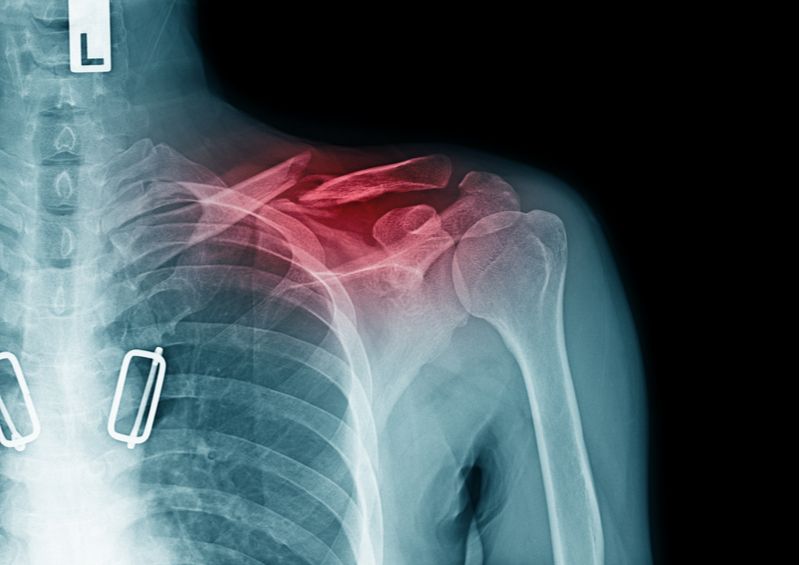

Repair of Clavicle Fractures

The clavicle, or collarbone, is broken most frequently in falls—from bikes, while skiing, and when doing other sports. A twisted, thin, flat bone, the clavicle presents lots of problems for surgeons trying to fix fractures. Here are some of the pitfalls.

The clavicle acts as a strut, reaching from the sternum to the scapular of the shoulder. It can be fractured by a fall or a direct blow. I broke mine when I fell face first skiing—while I was working, ironically, as an orthopaedic surgeon for a ski race. The walkie-talkie radio strapped to my chest was driven straight through my clavicle. Classically, surgeons have had three choices: leave the bones to heal on their own, fix the pieces with a steel plate and multiple screws, or place a screw lengthwise down the barrel of the bone.